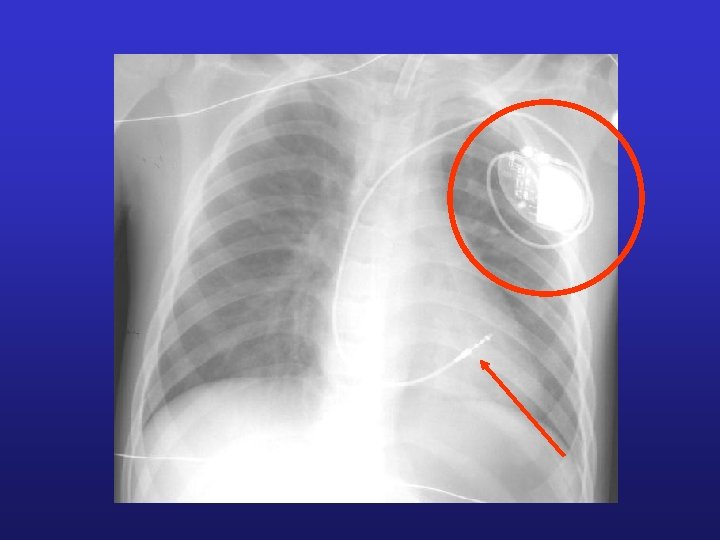

Anomalie dans le système de conduction peut entraîner des anomalies dans le déroulement de la révolution cardiaque. Peut nécessiter la mise en place d’un pacemaker

Fibrillation cardiaque = perte totale de la coordination des contractions Défibrillation suite à une fibrillation ventriculaire Fibrillation auriculaire